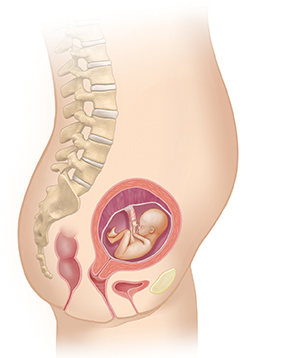

Month 4

Your baby’s heartbeat may be heard with a Doppler (handheld ultrasound device) by 9 to 10 weeks. Eyebrows, eyelashes, and fingernails begin to form.